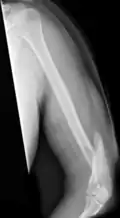

Midshaft humerus fracture with callus formation

Fractures of the humerus shaft are most often uncomplicated, closed fractures that require nothing more than pain medicine and wearing a cast or sling. For midshaft fractures up to 12 weeks may be required for healing.[17]